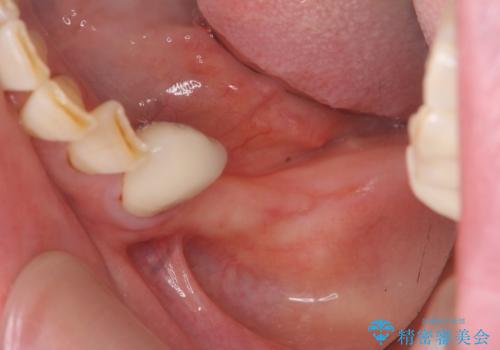

- 歯を虫歯により失い、「とりあえず入れ歯を入れたが,とにかく噛めず食事が全く楽しくない」またしっかりと噛みたいと希望され来院されました。

入れ歯を外し、またしっかりと噛んで食事を楽しめるようになるためにインプラントによる治療を計画します。